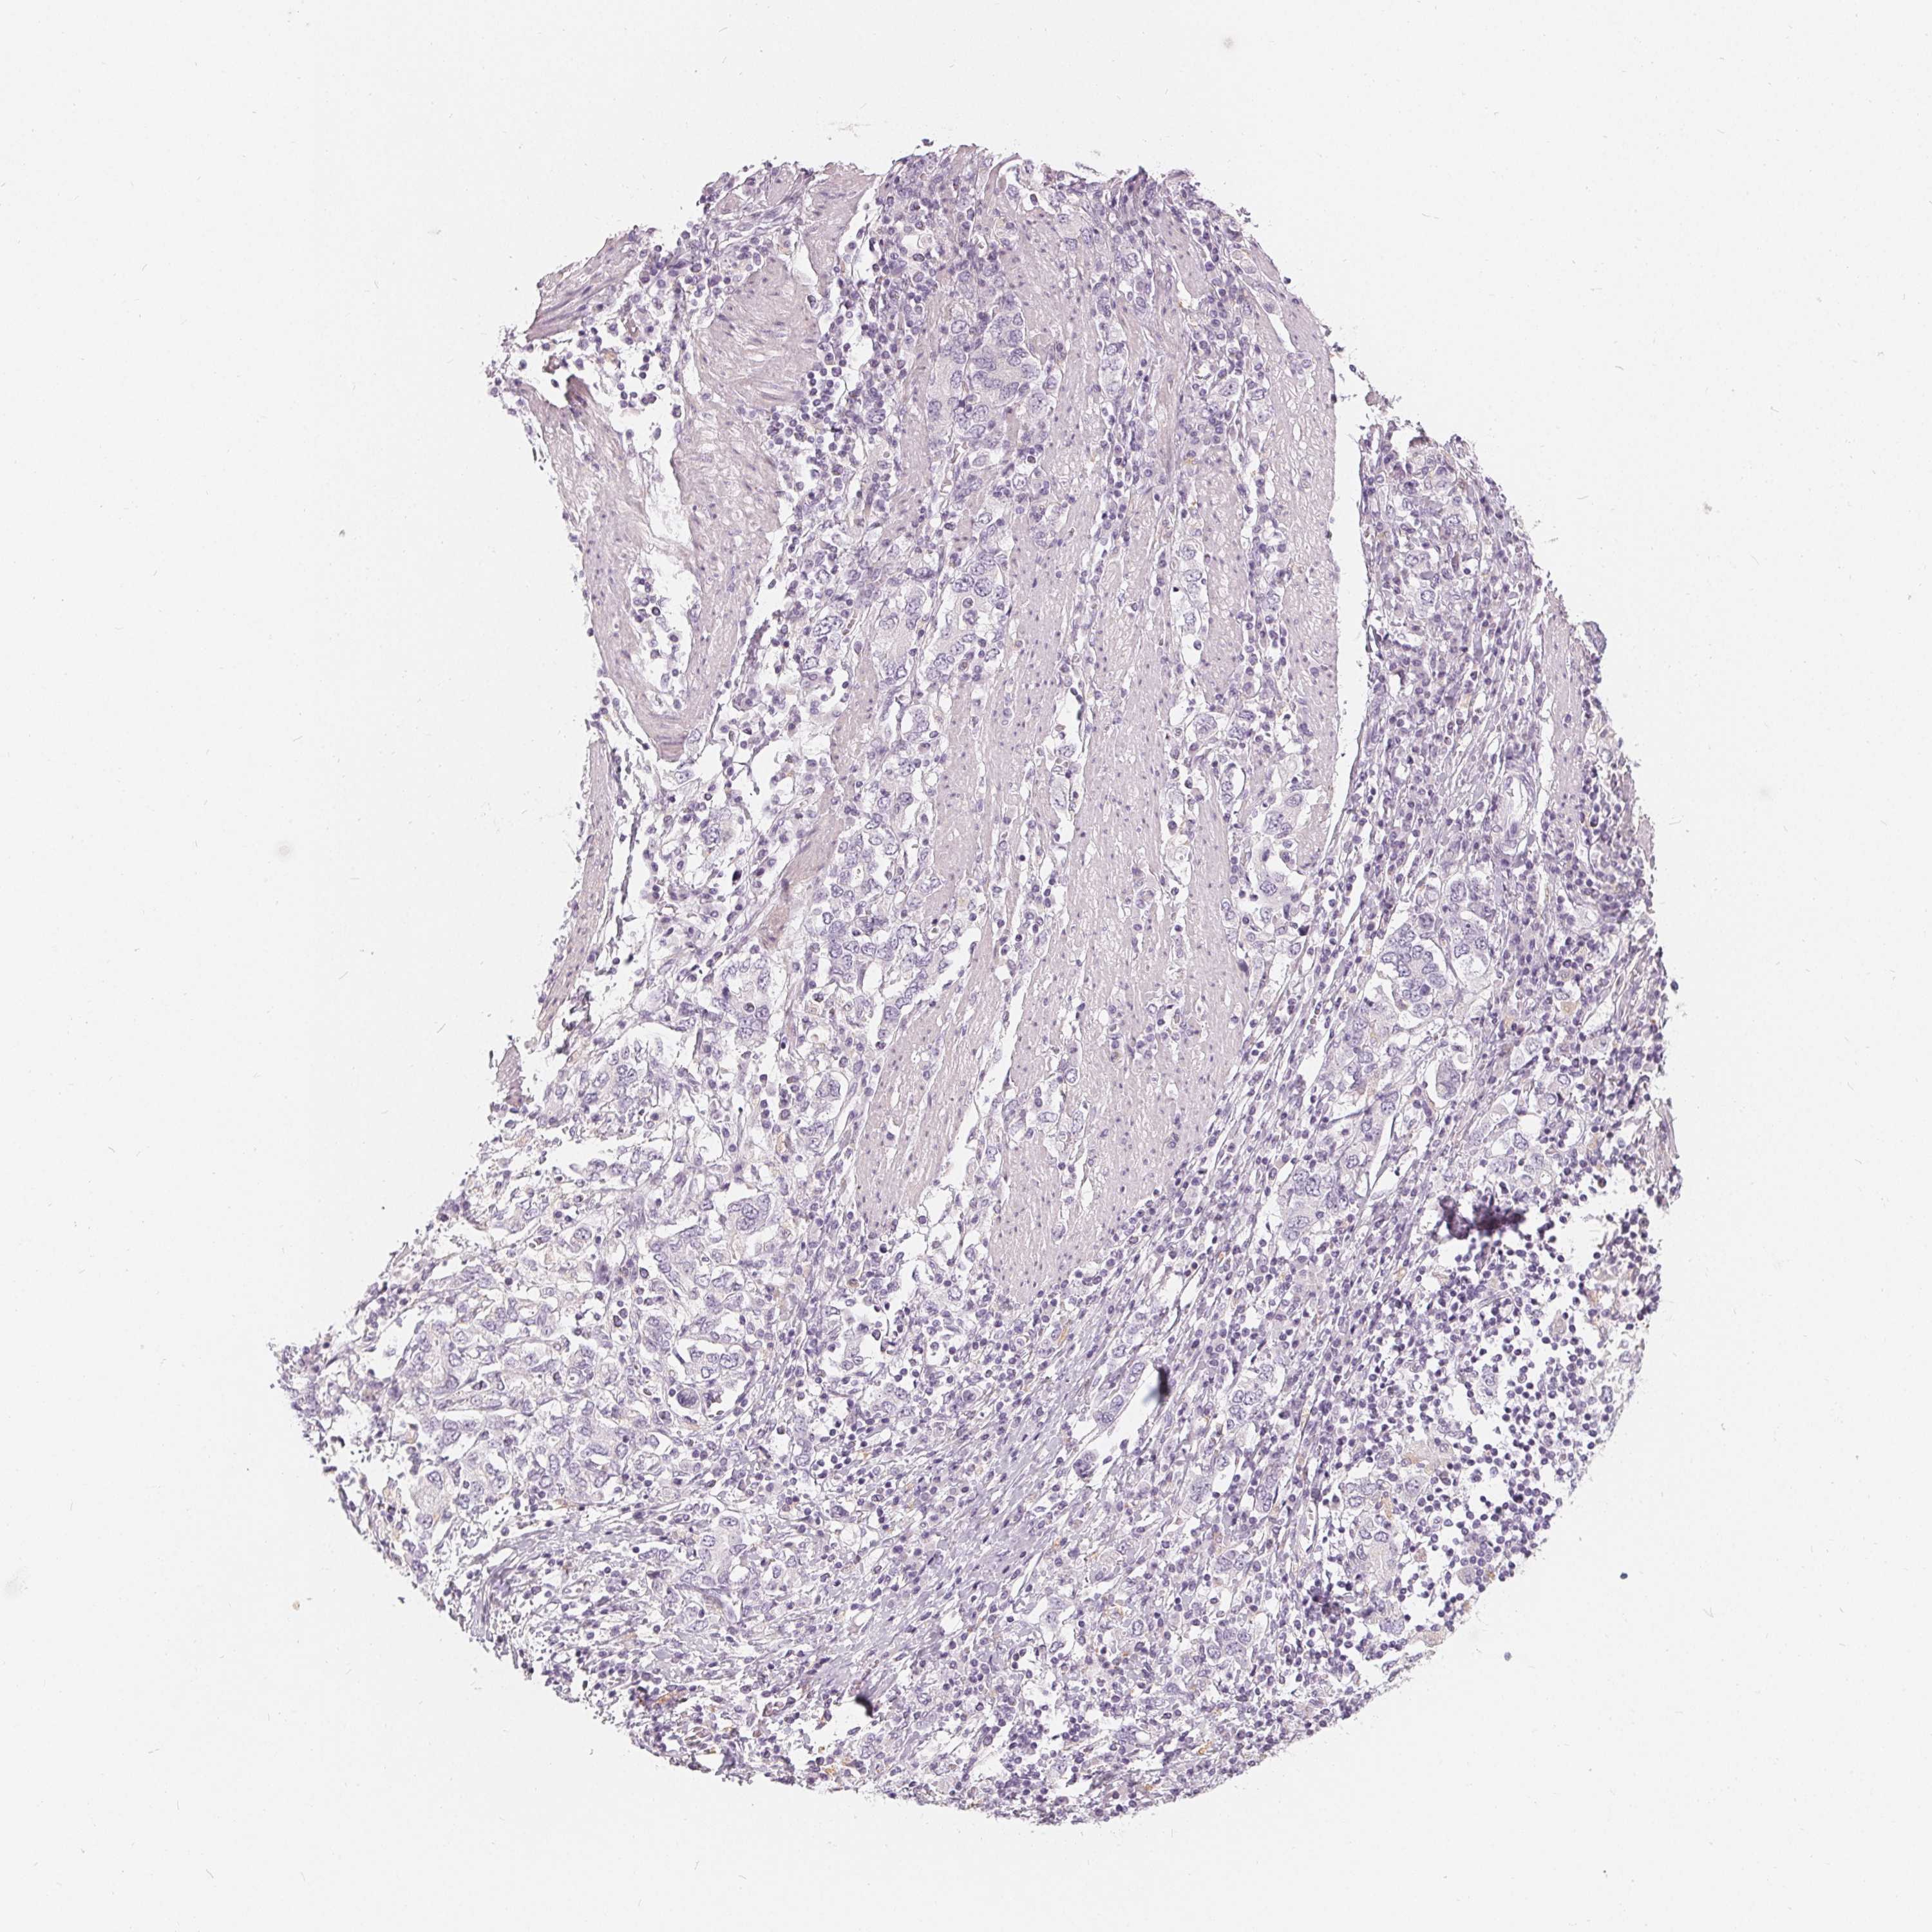

STOMACH CANCER - Protein expressioni

A mouse-over function shows sample information and annotation data. Click on an image to view it in a full screen mode. Samples can be filtered based on level of antibody staining by selecting one or several of the following categories: high, medium, low and not detected. The assay and annotation is described here.

Note that samples used for immunohistochemistry by the Human Protein Atlas do not correspond to samples in the TCGA dataset.

Antibody stainingi

Antibody staining in the annotated cell types in the current human tissue is reported as not detected, low, medium, or high, based on conventional immunohistochemistry profiling in selected tissues. This score is based on the combination of the staining intensity and fraction of stained cells.

Each image is clickable and will lead to virtual microscopy that enables deeper exploration of all samples and also displays staining intensity scores, fraction scores and subcellular localization as well as patient and tissue information for each sample.

Antibody HPA030180

Antibody CAB018632

Staining

High

Medium

Low

Not detected

Intensity

Strong

Moderate

Weak

Negative

Quantity

>75%

75%-25%

<25%

None

Location

Nuclear

Cytoplasmic/membranous

Cytoplasmic/membranous,nuclear

Adenocarcinoma, NOS